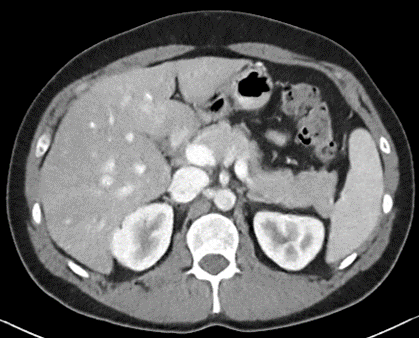

Figure 2: Comparison of generated Pseudo-LDCT images and their noise. (a) LDCT, (b) Random noise histogram, (c) Gaussian noise, (d) Ours. The right-bottom patch indicates the noise lying on each image. The noise quality of (b) and (c) shows that random noise cannot represent (a). In contrast, (d) shows almost similar to (a)

For evaluation, the 2016 AAPM Low-Dose CT Grand Challenge dataset[16] was used and split into 3 train and 7 test, respectively. It consists of abdominal LDCT and NDCT images obtained from 10 patients with image size 512×512512512512\times 512. The voxel space of CT images is 0.5mm×0.5mm0.5𝑚𝑚0.5𝑚𝑚0.5mm\times 0.5mm with 3mm3𝑚𝑚3mm slice thickness. To demonstrate that our method works with any existing learning method, we applied our method to N2C (Noise2Clean), N2N (Noise2Noise)[13], and N2V (Noise2Void)[11]. N2C is a supervised learning method that uses all available labeled paired data. N2N and N2V are self-supervised learning methods which use noisy pair images and masking schemes. Also, to demonstrate the effectiveness of our noise model, we compared LDCT denoising performance against existing noise generation techniques i.e. Random Noise histogram (Hist), Gaussian noise (Gaussian), and Single noise model++Noise histogram (Model+Hist). Hist samples noise from the difference map based on the histogram between LDCT and NDCT images, whereas gaussian samples the noise from a Gaussian distribution with zero mean and 0.02 standard deviation. Model+Hist is the combination of a single pre-trained LDCT noise model (using all subjects in the training dataset) and Hist. For evaluation, Peak Signal-to-Noise Ratio (PSNR) and Structural Similarity (SSIM) are reported.

For parameter updates, it is crucial to generate high-quality Pseudo-LDCT images i.e. images similar to an actual LDCT image. If high-quality Pseudo-LDCT images are provided to the model for training, CT denoising performance can be improved. In contrast, using low-quality Pseudo-CT images may adversely affects the model learning, and consequently lead to decreased denoising performance. Table. 1 also shows the average PSNR and SSIM in different Pseudo-CT image generation settings. Here, both Hist and Gaussian reported lower performance compared to N2C. Based on our observations, this serves to show that random noise employed in natural images is not useful for CT denoising. In contrast, when our noise model was combined with Hist i.e. Model+Hist, performance gains over N2C were noted. This implies that our noise model can generate reasonable noise similar to the actual CT noise, and also improves performance. Furthermore, our ensemble noise models without parameter update show improved results over Model+Hist without the need for additional random noise.

In Figures 2 and 3, we show comparison results of Pseudo-LDCT images and their generated noise using various methods, as well as the predictions of our method for each. In Fig. 2, Pseudo-LDCT images and their noise with Hist and Gaussian highlight a huge discrepancy between the actual LDCT image and its noise. In the case of random noise that is shown to be independently distributed across the entire image, it is often useful for natural image denoising. Moreover, this types of noise does not accurately reflect the nature of CT images. Through the proposed method, we show it is possible to generate Pseudo-CT images that preserve overall CT image characteristics with high quality (Fig. 3).